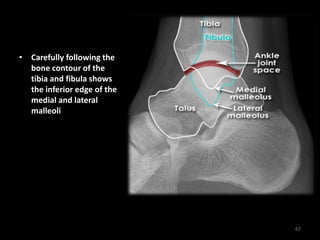

Ankle anatomy - Normal

Lateral

66

• Carefully following the

bone contour of the

tibia and fibula shows

the inferior edge of the

medial and lateral

malleoli

67